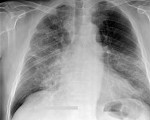

- Рентгенография. Рентгенологическими признаками интерстициальной пневмонии могут являться симметричные полупрозрачные затемнения по типу «матового стекла», в основном в нижних отделах легких; утолщение междолькового и внутридолькового интерстиция; кистозно-фиброзные изменения, периваскулярная и перибронхиальная инфильтрация и тракционные бронхоэктазы.

- Рентгенографическое и рентгеноскопическое исследования органов грудной клетки – обнаружение утолщенных соединительнотканных перегородок между долями и внутри них, симметричных полупрозрачных затемнений по типу «матового стекла», кистозно-фиброзных изменений, периваскулярной и перибронхиальной инфильтрации.